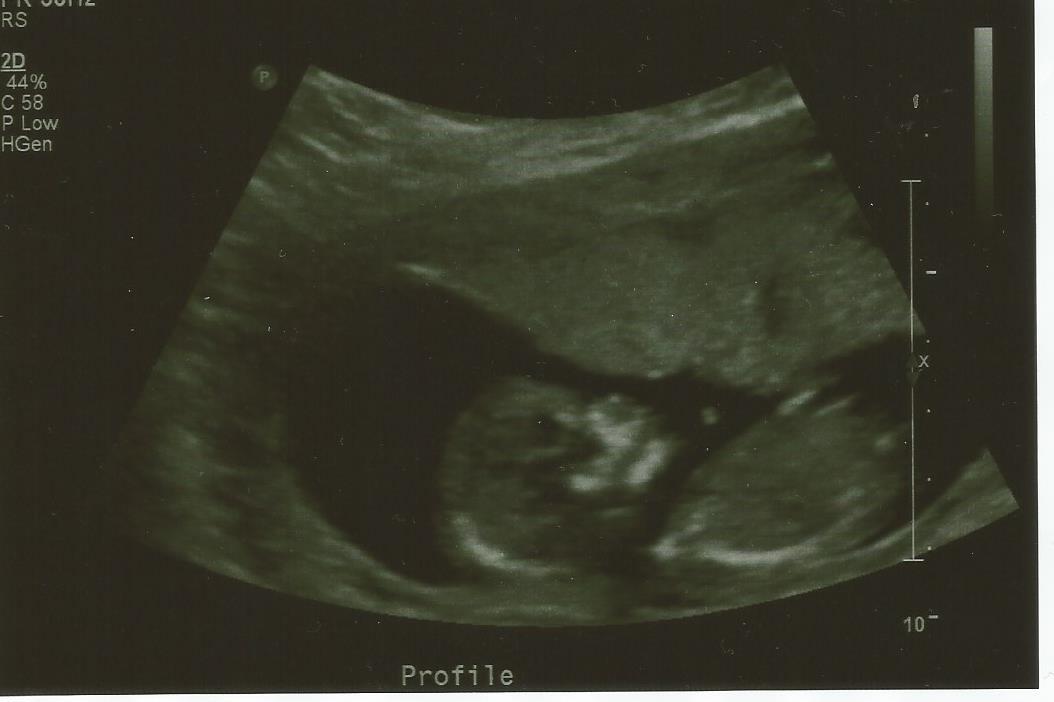

meant to add these pics are 13w 4days

Probably a baby boy

Getting a boy vibe from these too. Did you sway? Curious as I noticed the names as at the bottom of your first pic.

Actually No MiaMelb. We were trying to conceive again since October and I was beginning to lose hope when it happened in April. My period was different before i conceived and I usually would ovulate on day 17 and I did on day 18. Just curious if you think the thing sticking up is a boy nub and nothing else? Me and the husband have been arguing over this lol Funny thing is I told myself that I wanted another girl cause I am so used to girls lol.